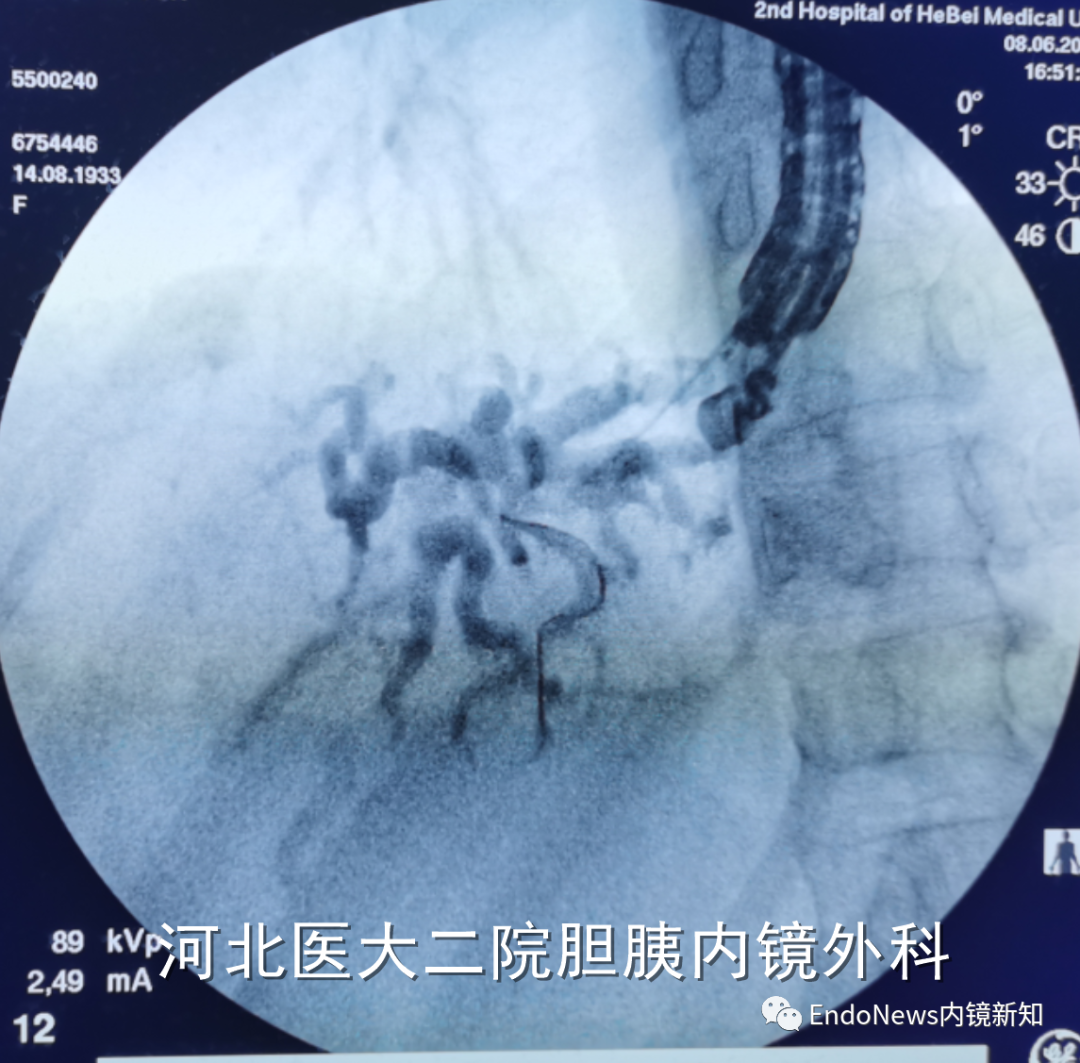

行经十二指肠胆管穿刺(CDS)时一般不需要考虑以上问题,但如因某些特殊原因涉及到会师操作时可能涉及到导丝自胆总管上游朝向下游的超选。一般情况下,CDS的时候穿刺针的方向是朝向肝内的,比如下图:

如果这个时候放支架行CDS就可以结束手术了,如果需要做顺行或者会师,就需要使导丝返折180°朝向胆管下游方向穿出十二指肠乳头。